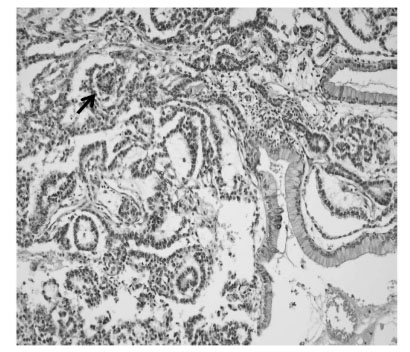

Fig. 2); sectioning revealed semisolid grayish material and cartilaginous tissue. Pathologic examination revealed a mixed malignant GCT made of two components, a mainly endodermal sinus tumor and a small mature teratoma. We also observed a loose reticular pattern and rounded papillary processes with central capillary, Schiller-Duval bodies. The tumor was immunohistochemically positive for AFP. The resected hepatic specimen was a metastasis of the mixed GCT and was histologically identical to that component of the primary tumor (

Fig. 3Microscopic examination, showing that the primary tumor was composed primarily of endodermal sinus tumor components. A loose reticular pattern and rounded papillary processes with central capillary, "Schiller-Duval bodies" were also observed (arrow). The section from the liver shows a metastatic germ cell tumor, composed primarily of an endodermal sinus tumor component (H & E, × 200 magnification).